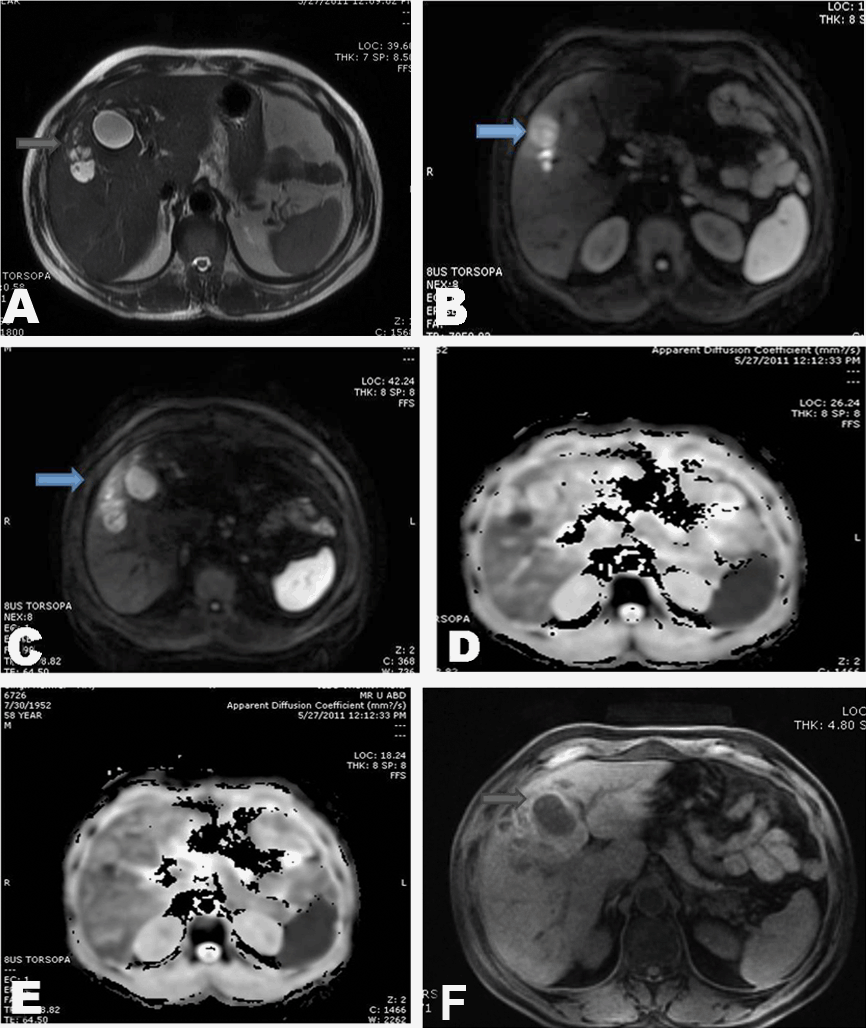

Case 2: Fifty-eight years male with low grade fever off and on for past three months was investigated and found to have raised total leukocyte count of 11,500/mm3, high ESR - 70 mm/1st hr, increased eosinophil count (38%) with altered liver enzymes and mildly raised total bilirubin of 2.5 mg/dl. His hydatid serology was negative. MRI was done for evaluation and multiple well defined thick walled T2 hyperintense lesions (Figure 2A) with brightness on diffusion weighted images (b value 1000) (Figure 2B, C) and corresponding restriction on ADC was seen (Figure 2D, E). In addition these lesions had T1 hyperintensity along their peripheries Figure 2F), possibly due to high cellularity. Parasitic eosinophilic abscesses due to VLM were diagnosed in correlation with peripheral eosinophilia.

Anti-helminthic treatment showed significant decrease in lesion size and clinical symptoms.

Figure 2: A) T1 weighted axial sequence of the liver MRI at 3T shows hypointense conglomerating ovoid lesions with peripheral hyperintense rim, B) T2 weighted SSFSE sequence shows hyperintense lesions of varying sizes 1–2.5 cms appearing as a cluster, C, D) DWI at b value of 1000 shows hyperintensity of the above lesions, which are well appreciated on these images, E, F) ADC maps of the above lesions show areas of restriction appearing hypointense within the lesions in the right lobe.